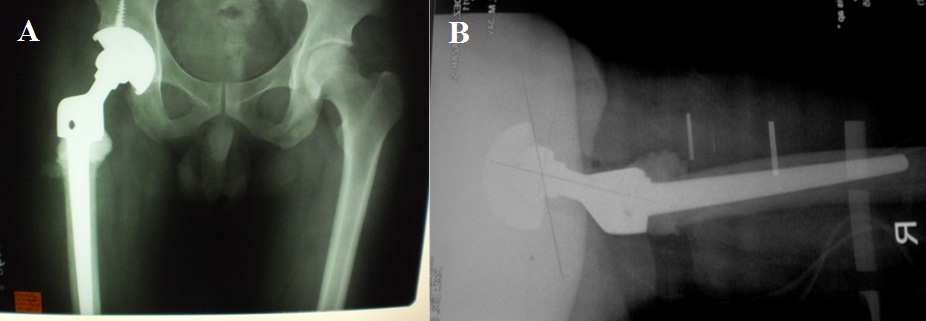

Two weeks prior to surgery, the patient’s pain increased in intensity up to a VAS score of 9/10. He did not recall any incident of fall or trauma. His limp worsened and was unable to put weight on his right lower extremity. He was eventually brought to our institution’s out-patient clinic. After initial assessment from the clinic’s triage, the patient was referred to our institution’s orthopedic and musculoskeletal tumor service. Physical examination done both by the orthopedic-musculoskeletal tumor specialist and orthopedic resident, indicated leg length shortening of 0.5 cm on the right lower extremity, right hip tenderness upon palpation, and a positive heel pound test. No skin lesions, palpable mass, nor lymphadenopathy were noted. The modified Musculoskeletal Tumor Society rating functional (MSTS) score was 4/30. Repeat plain radiographs of the hip revealed a pathologic fracture of the right femoral neck at the area of the lesion (Figure 1). The proximal femoral lesion was characterized as epi-metaphyseal, osteolytic with well demarcated borders, with endosteal expansion, cortical break, and has soft tissue extension anteriorly; but without any matrix. The lesion extended from the femoral neck up to the base of the lesser trochanter. The patient was admitted for further work-up and his right lower extremity was placed in skin traction. Magnetic resonance imaging of the hip confirmed a well delineated homogenous 8x7 cm lesion from the greater trochanter up to the level of the base of the lesser trochanter (Figure 2). A pre-operative tru-cut biopsy was done in the ward to exclude other differential diagnosis such as aneurysmal bone cyst and other primary bone tumor. The results confirmed giant cell tumor of the bone. The radiologic grade of the tumor was a Campanacci III due to the anterior cortical break and soft tissue extension, while the clinical and histologic grade was an Enneking 3 (for benign lesions). A pre-operative chest X-ray was done to rule out pulmonary metastasis, and showed negative results. The authors decided to pursue wide excision and perform total hip replacement due to the patient’s age and function, high recurrence for GTCb, along with the extensiveness of the lesion and the cortical break. Prosthesis specifications that were considered included a custom-made proximal femur endoprosthesis or a proximal femoral allograft composite. However, due to financial constraints and unavailability of a proximal femur allograft, a calcar-replacing femoral stem was selected due to the involvement and possible excision of the calcar femorale and lesser trochanter.

The patient was placed on lateral decubitus position under general anaesthesia. A curvilinear longitudinal skin incision was made starting proximal to the greater trochanter and following a parallel course to the femoral shaft. After retraction of the subcutaneous tissue, careful dissection was carried out to perform a wide resection of the proximal femur lesion up to 1.5 cm distal to the base of the lesser trochanter including the insertion of iliopsoas, vastus lateralis, gluteus medius, short external rotators, and proximal portion of tensor fascia lata. The proximal femur lesion was separated distally from the shaft with the use of an oscillating saw, while the femoral head was dislocated from the acetabulum (Figure 3). An intralesional tissue sample was sent for frozen section to confirm diagnosis, while surrounding soft tissue samples were sent to check adequacy of resection margins. An uncemented press-fit grit-blasted titanium acetabular cup, coated with hydroxyapatite (Figure 4), was inserted along with titanium cancellous screws (United Orthopedic Corporation, Taiwan). This was mounted with an Ultra High Molecular Weight (UHMW) polyethylene acetabular liner fitted with a BIOLOX™ (United Orthopedic Corporation, Taiwan) ceramic head. For the femoral stem, a 160 mm long cobalt chrome GTF calcar-replacing femoral stem (United Orthopedic Corporation, Taiwan) was inserted with a 2nd generation cementing technique. Excess cement was moulded around the junction between the femoral shaft and the calcar component of the implant (Figure 5). The gluteus medius and iliopsoas were attached to the hole on the proximal part of the femoral component using Ethibond Excel™ sutures. The vastus lateralis was sutured to the tensor fascia lata. A drain was positioned beneath the tensor fascia lata prior to skin closure. There was a leg lengthening of 0.5 cm of the operated limb on inspection, andan abduction pillow was placed between the patient’s legs post-operatively. Prophylactic deep venous thrombosis management have been routinely administered. The patient was instructed touch-weight bearing for up to two weeks, and progressively improved to full weight bearing in 6 weeks post-op. The final histopathology report noted osteoclastic giant cells sporadically distributed throughout the stromal cells which confirmed the diagnosis of GCTb (Figure 6). The stromal cells were comprised of mononuclear round cells, instead of the spindle-shaped variant which is associated with the risk of malignant transformation [1]. His succeeding follow-up appointments at two weeks, first month, 3rd month, and 6th month post op were straightforward. His latest follow-up was at one year post-op, where the patient was ambulating full weight-bearing and without use of any assistive device. The patient walked without limp and only had a slight Trendelenberg sign on physical exam (Figure 7). The most recent radiographs showed no implant loosening, peri-prosthetic fracture, nor any evidence of tumor recurrence (Figure 8). A repeat chest radiograph noted no evidence of metastasis. The latest musculoskeletal tumor society rating functional score improved to 28/30 on latest follow-up.

Figure 2: Magnetic resonance imaging coronal T1 image demonstrates a well delineated homogenous 8x7 cm lesion from the greater trochanter up to the level of the base of the lesser trochanter.

Figure 4: Total hip replacement implants used: A) An uncemented grit-blasted titanium acetabular cup, coated with hydroxyapatite, B) A 160 mm long cobalt chrome GTF calcar-replacing femoral stem.

Figure 5: Arrow pointer showing excess cement that was moulded around the junction between the femoral shaft and the calcar component of the implant.